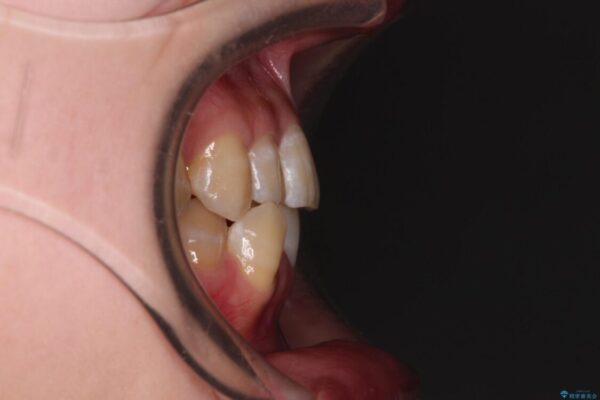

治療後

• 【モニター】下顎前歯のデコボコをインビザラインできれいに 治療後画像

治療前、下顎前歯のデコボコが集中しており、奥歯の咬み合わせは、上顎に対して下顎が前方位にある状態でした。下顎の歯列を後方へ移動させる治療はインビザラインの得意とするところですので、1年程度で無事に治療を終えることができました。